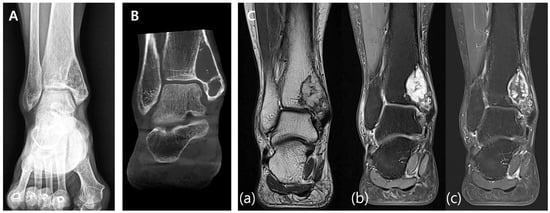

An 81-year-old male presented with left-ankle pain following a fall. The patient had a history of stage-IIA non-small-cell lung carcinoma (NSCLC) treated with intensity-modulated radiation therapy nine months earlier. Preoperative imaging revealed a lytic lesion with cortical thinning and a fracture line in the distal third of the fibular shaft (Figure 9A,B). MRI revealed a 3.5 cm lobulated mass with central necrosis and prominent extraosseous extension. The signal characteristics were consistent with metastatic disease, as demonstrated via T2-weighted imaging showing a hypointense lobulated mass with irregular margins and through contrast-enhanced T1-weighted imaging displaying heterogeneous intermediate-to-low signal intensity with central necrotic areas and extraosseous extension (Figure 9C). Based on the imaging results and clinical history, the lesion was diagnosed as a pathological fracture secondary to metastatic lung cancer.

Figure 9. Preoperative imaging. (A) Preoperative X-ray showing a lytic lesion in the distal third of the fibula with cortical thinning and a visible fracture line. (B) Preoperative CT scan illustrating the lesion’s cortical destruction, dimensions, and evidence of a pathological fracture. (C) Preoperative MRI. (a) T2-weighted image demonstrating a hypointense lobulated mass with irregular margins. (b) Contrast-enhanced T1-weighted image showing heterogeneous intermediate-to-low signal intensity with central necrotic areas and prominent extraosseous extension.